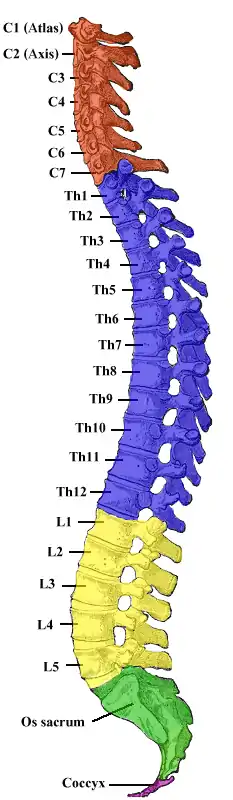

Syringomyelia is a generic term referring to a disorder in which a cyst or cavity forms within the spinal cord. Often, syringomyelia is used as a generic term before an etiology is determined.[3] This cyst, called a syrinx, can expand and elongate over time, destroying the spinal cord. The damage may result in loss of feeling, paralysis, weakness,[4] and stiffness in the back, shoulders, and extremities. Syringomyelia may also cause a loss of the ability to feel extremes of hot or cold, especially in the hands. It may also lead to a cape-like bilateral loss of pain and temperature sensation along the upper chest and arms. The combination of symptoms varies from one patient to another depending on the location of the syrinx within the spinal cord, as well as its extent.

Syringomyelia has a prevalence estimated at 8.4 cases per 100,000 people,[5] with symptoms usually beginning in young adulthood. Signs of the disorder tend to develop slowly, although sudden onset may occur with coughing, straining, or myelopathy.

Syringomyelia causes a wide variety of neuropathic symptoms, due to damage to the spinal cord. Patients may experience severe chronic pain, abnormal sensations and loss of sensation, particularly in the hands. Some patients experience paralysis or paresis, temporarily or permanently. A syrinx may also cause disruptions in the parasympathetic and sympathetic nervous systems, leading to abnormal body temperature or sweating, bowel control issues, or other problems. If the syrinx is higher up in the spinal cord or affecting the brainstem, as in syringobulbia, vocal cord paralysis, ipsilateral tongue wasting, trigeminal nerve sensory loss, and other signs may be present.[6] Rarely, bladder stones can occur at the onset of weakness in the lower extremities.[7] Classically, syringomyelia spares the dorsal column/medial lemniscus of the spinal cord, leaving pressure, vibration, touch and proprioception intact in the upper extremities. Neuropathic arthropathy, also known as a Charcot joint, can occur, particularly in the shoulders, in patients with syringomyelia.[8] The loss of sensory fibers to the joint is theorized to lead to degeneration of the joint over time.[9]

Generally, there are two forms of syringomyelia: congenital and acquired. Syringomyelia is generally a chronic disorder that occurs over time, resulting in muscular atrophy. Acquired Syringomyelia can be caused by a serious physical trauma to the body such as in a road traffic accident. Syringomyelia can also be classified into communicating and noncommunicating forms. Communicating typically occurs due to lesions on the foramen magnum and noncommunicating occurring due to other spinal cord diseases.[10]

The first major form relates to an abnormality of the brain called an Arnold–Chiari malformation or Chiari malformation. This is the most common cause of syringomyelia, where the anatomic abnormality, which may be due to a small posterior fossa, causes the lower part of the cerebellum to protrude from its normal location in the back of the head into the cervical or neck portion of the spinal canal. A syrinx may then develop in the cervical region of the spinal cord. Here, symptoms usually begin between the ages of 25 and 40 and may worsen with straining, called a valsalva maneuver, or any activity that causes cerebrospinal fluid pressure to fluctuate suddenly. Some patients, however, may have long periods of stability. Some patients with this form of the disorder also have hydrocephalus, in which cerebrospinal fluid accumulates in the skull, or a condition called arachnoiditis, in which a covering of the spinal cord—the arachnoid membrane—is inflamed.[11] Some cases of syringomyelia are familial, although this is rare.[12]

The second major form of syringomyelia occurs as a complication of trauma, meningitis, hemorrhage, a tumor, or arachnoiditis. Here, the syrinx or cyst develops in a segment of the spinal cord damaged by one of these conditions. The syrinx then starts to expand. This is sometimes referred to as noncommunicating syringomyelia. Symptoms may appear months or even years after the initial injury, starting with pain, weakness, and sensory impairment originating at the site of trauma.[13]

The possible causes are trauma, tumors, and congenital defects. It is most usually observed in the part of the spinal cord corresponding to the neck area. Symptoms are due to spinal cord damage and include pain, decreased sensation of touch, weakness, and loss of muscle tissue. The diagnosis is confirmed with a spinal CT, myelogram or MRI of the spinal cord. The cavity may be reduced by surgical decompression.[23]